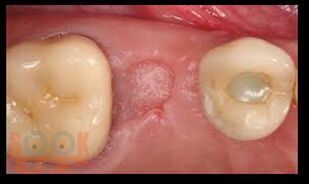

В предлагаемом учебном пособии рассмотрены основные вопросы местного обезболивания, применяемого в стоматологической практике на амбулаторном прием. Приведены характеристики современных местноанестезирующих препаратов и пути их введения. Описаны и продемонстрированы в иллюстрациях ряд хирургических стоматологических операций.